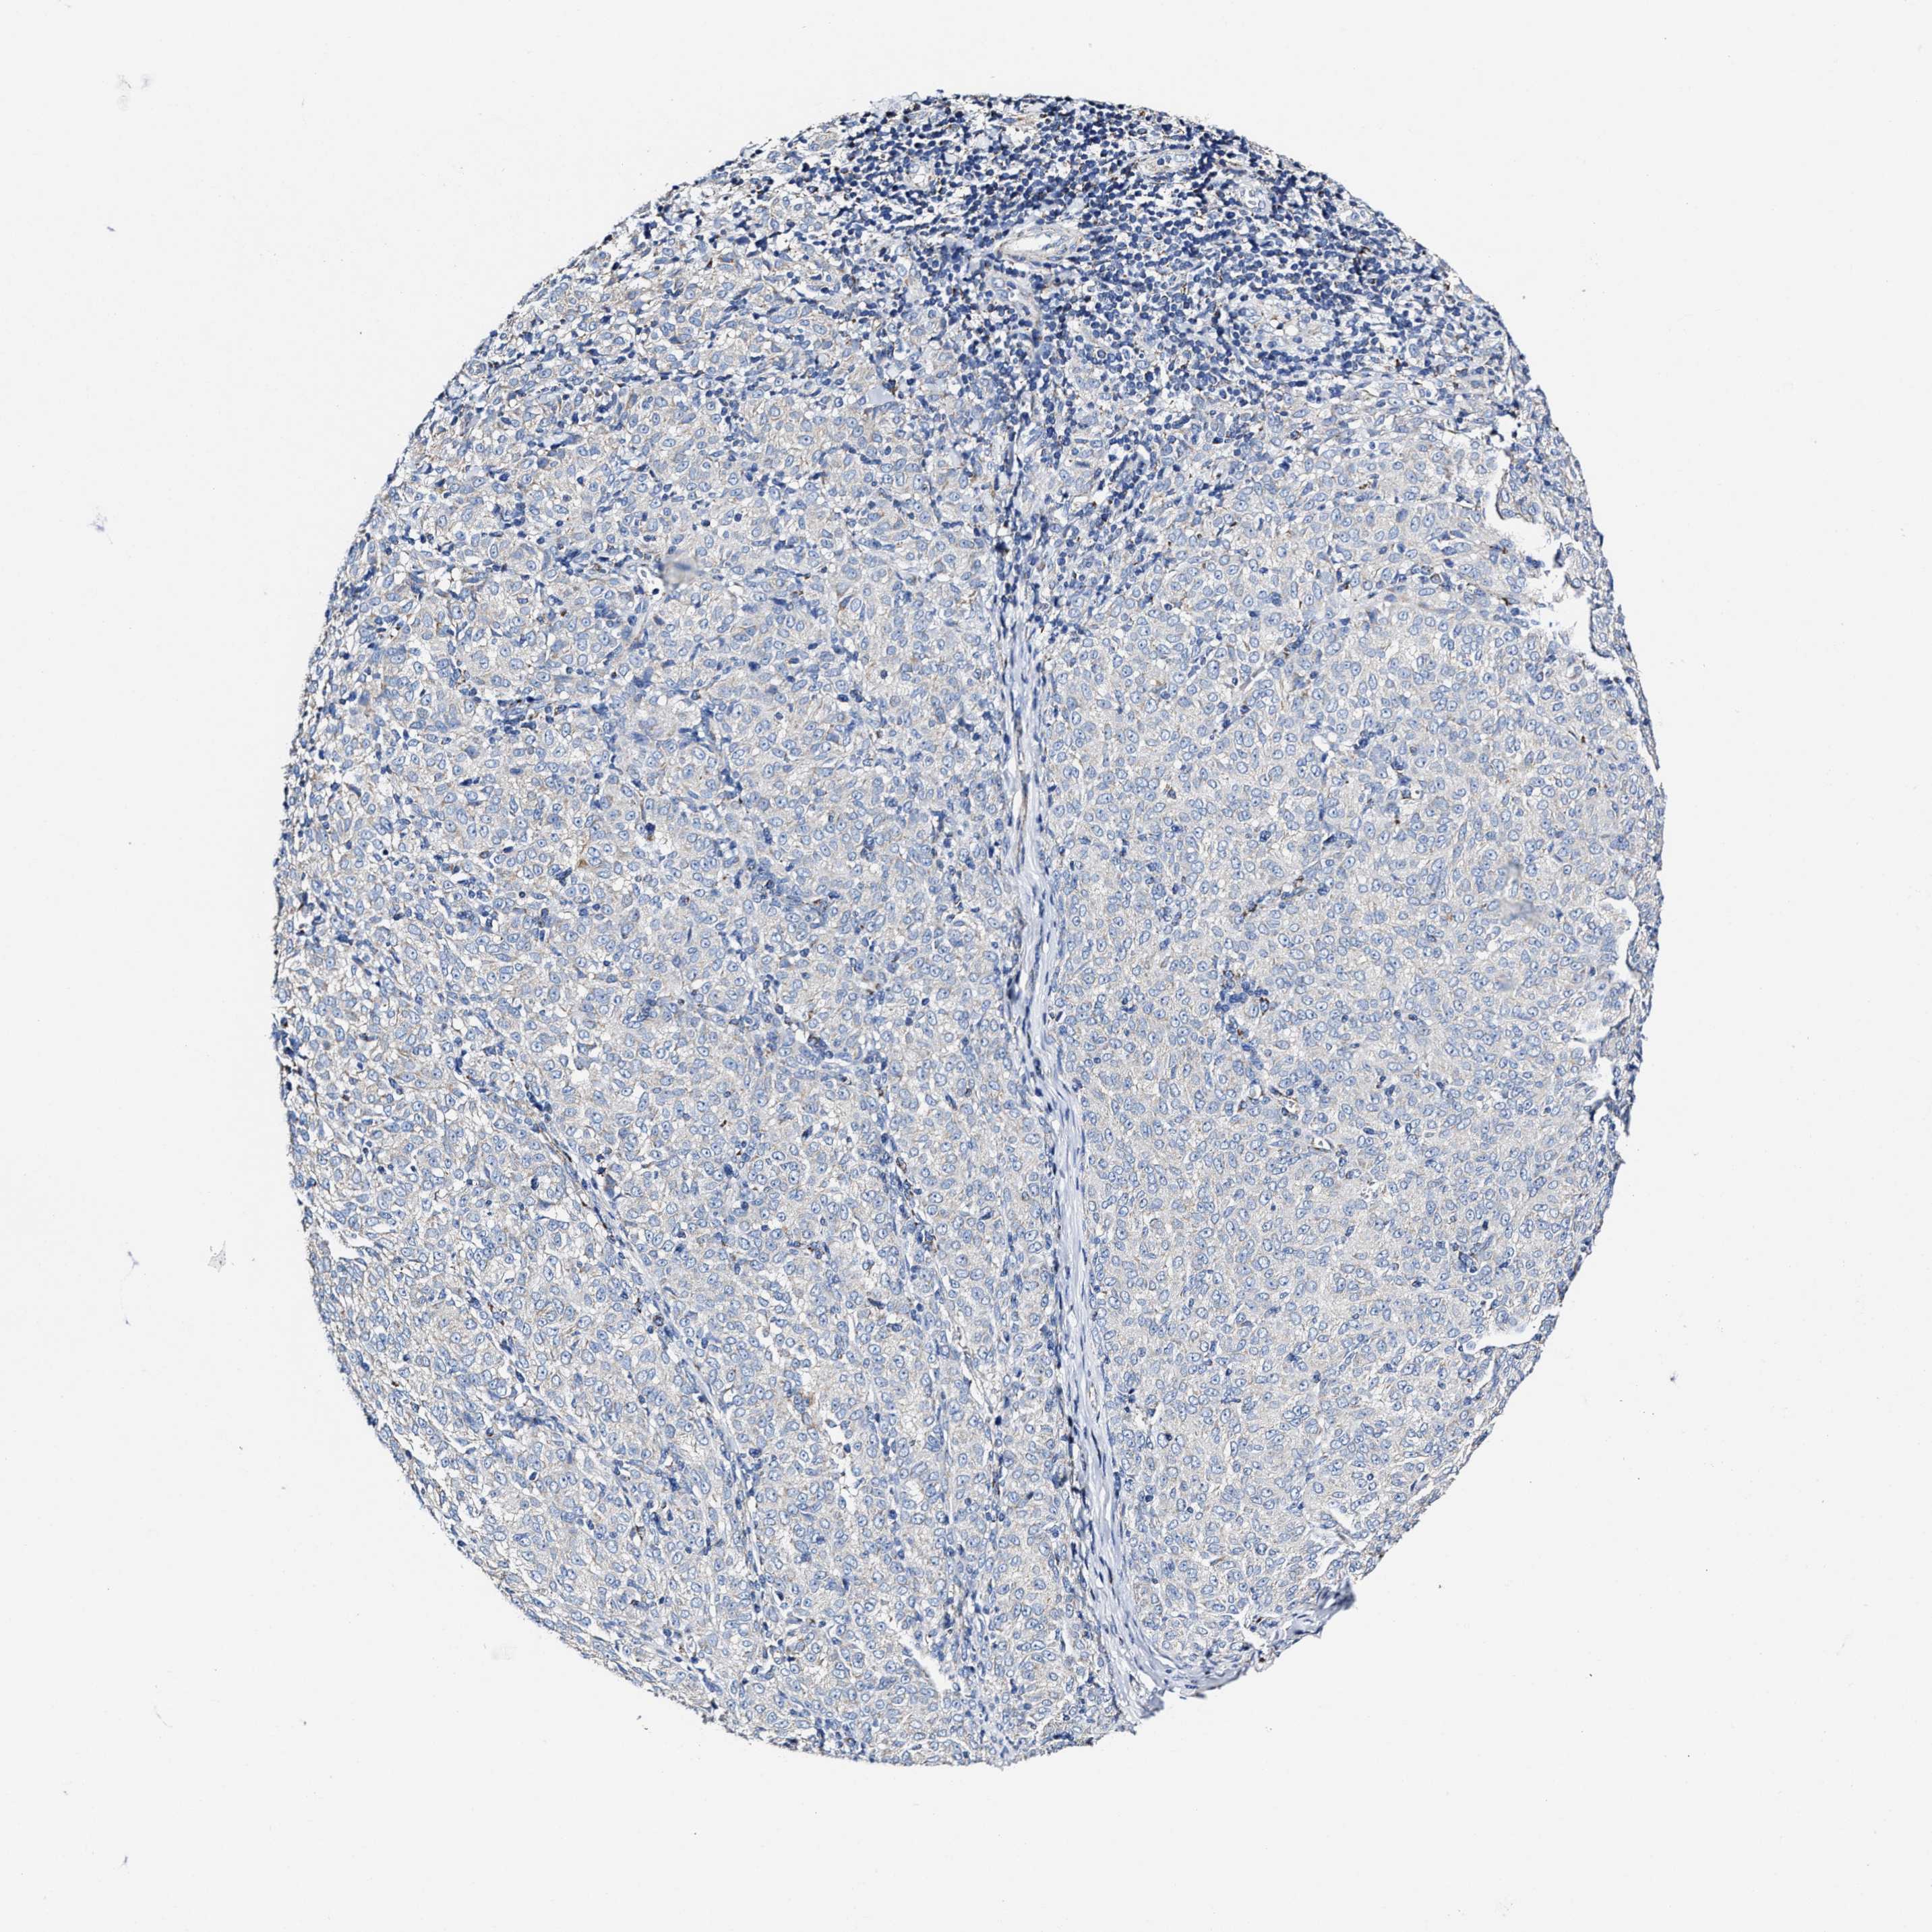

MELANOMA - Protein expressioni

A mouse-over function shows sample information and annotation data. Click on an image to view it in a full screen mode. Samples can be filtered based on level of antibody staining by selecting one or several of the following categories: high, medium, low and not detected. The assay and annotation is described here.

Note that samples used for immunohistochemistry by the Human Protein Atlas do not correspond to samples in the TCGA dataset.

Antibody stainingi

Antibody staining in the annotated cell types in the current human tissue is reported as not detected, low, medium, or high, based on conventional immunohistochemistry profiling in selected tissues. This score is based on the combination of the staining intensity and fraction of stained cells.

Each image is clickable and will lead to virtual microscopy that enables deeper exploration of all samples and also displays staining intensity scores, fraction scores and subcellular localization as well as patient and tissue information for each sample.

Antibody HPA020961

Antibody HPA059109

Staining

High

Medium

Low

Not detected

Intensity

Strong

Moderate

Weak

Negative

Quantity

>75%

75%-25%

<25%

None

Location

Nuclear

Cytoplasmic/membranous

Cytoplasmic/membranous,nuclear

Malignant melanoma, NOS

Malignant melanoma, Metastatic site